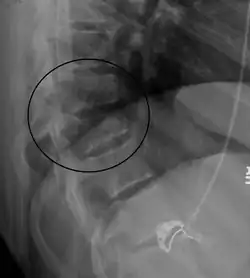

| A Chance fracture of T10 and fracture of T9 due to a seatbelt during an MVC. | |

A Chance fracture is a type of vertebral fracture that results from excessive flexion of the spine.[8][9] Symptoms may include abdominal bruising (seat belt sign), or less commonly paralysis of the legs.[4][10] In around half of cases there is an associated abdominal injury such as a splenic rupture, small bowel injury, pancreatic injury, or mesenteric tear.[3][5] Injury to the bowel may not be apparent on the first day.[11]

The cause is classically a head-on motor vehicle collision in which the affected person is wearing only a lap belt.[2] Being hit in the abdomen with an object like a tree or a fall may also result in this fracture pattern.[12][10] It often involves disruption of all three columns of the vertebral body (anterior, middle, and posterior).[7][6] The most common area affected is the lower thoracic and upper lumbar spine.[6] A CT scan is recommended as part of the diagnostic work-up to detect any potential abdominal injuries.[5] The fracture is often unstable.[1]

On plain X-ray, a Chance fracture may be suspected if two spinous processes are excessively far apart.[10]